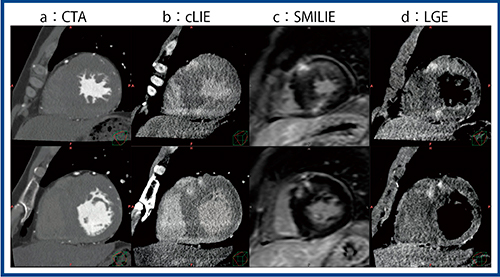

症例2は,左室肥大と不整脈で当施設に紹介された(図4)。冠動脈には問題がなかったが,左室流出路の最大圧較差(peak pressure gradient:PPG)の上昇と中隔肥大(asymmetric septal hypertrophy:ASH)が認められ,心臓CTを施行した。心臓CTでは左室に肥大が認められ(図4 a),cLIE(図4 b)でも染まりがわかるが,SMILIE(図4 c)では明瞭に描出された。MRIのLGE(図4 d)でも,同様の部位に同じような造影効果が認められ,肥大型心筋症と診断された。

図4 症例2:左室肥大と不整脈